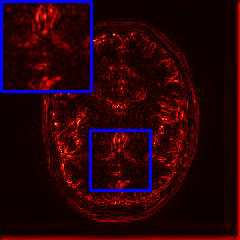

Limited by imaging systems, the reconstruction of Magnetic Resonance Imaging (MRI) images from partial measurement is essential to medical imaging research. Benefiting from the diverse and complementary information of multi-contrast MR images in different imaging modalities, multi-contrast Super-Resolution (SR) reconstruction is promising to yield SR images with higher quality. In the medical scenario, to fully visualize the lesion, radiologists are accustomed to zooming the MR images at arbitrary scales rather than using a fixed scale, as used by most MRI SR methods. In addition, existing multi-contrast MRI SR methods often require a fixed resolution for the reference image, which makes acquiring reference images difficult and imposes limitations on arbitrary scale SR tasks. To address these issues, we proposed an implicit neural representations based dual-arbitrary multi-contrast MRI super-resolution method, called Dual-ArbNet. First, we decouple the resolution of the target and reference images by a feature encoder, enabling the network to input target and reference images at arbitrary scales. Then, an implicit fusion decoder fuses the multi-contrast features and uses an Implicit Decoding Function~(IDF) to obtain the final MRI SR results. Furthermore, we introduce a curriculum learning strategy to train our network, which improves the generalization and performance of our Dual-ArbNet. Extensive experiments in two public MRI datasets demonstrate that our method outperforms state-of-the-art approaches under different scale factors and has great potential in clinical practice.